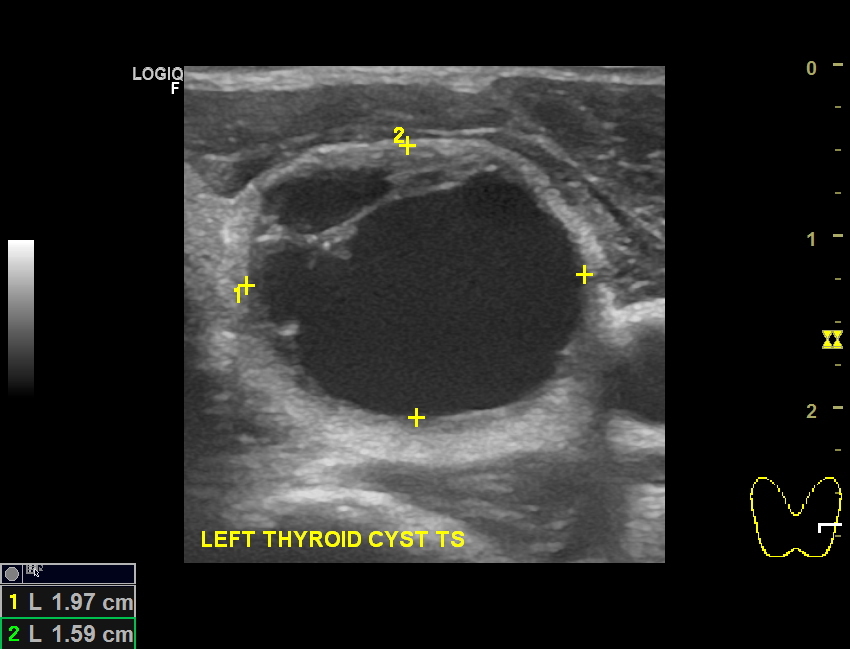

Thyroid Cysts Radiology Key Thyroid Nodule Vs Cyst A thyroid ultrasound provides the best information about the shape and structure of nodules. What are the main causes of enlargement of the thyroid gland? An ultrasound and sometimes a biopsy are needed to determine if a nodule is malignant. Thyroid cancers can appear similar to any of the other types of thyroid nodules. Because many thyroid nodules don’t have. Thyroid Nodule Vs Cyst.